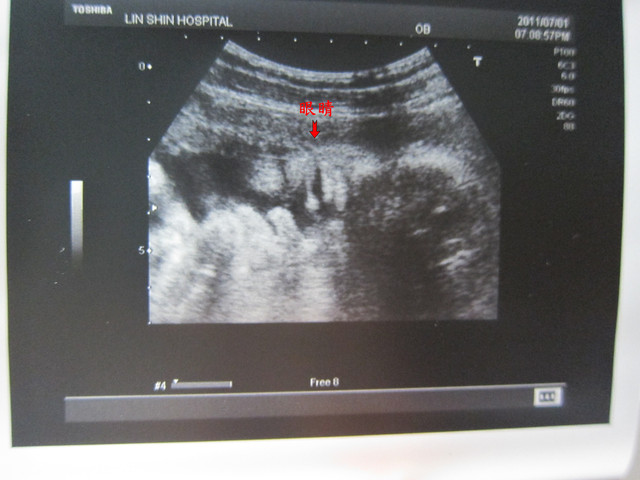

當醫師量完體重之後,鏡頭轉往兔胚臉的時候

發現這小子大大的打了個大呵欠!

是有沒有那麼累呀?

不過,剛好捕捉到兔胚打呵欠的影片

覺得好可愛唷!

上次是眨眨眼,這次是打呵欠